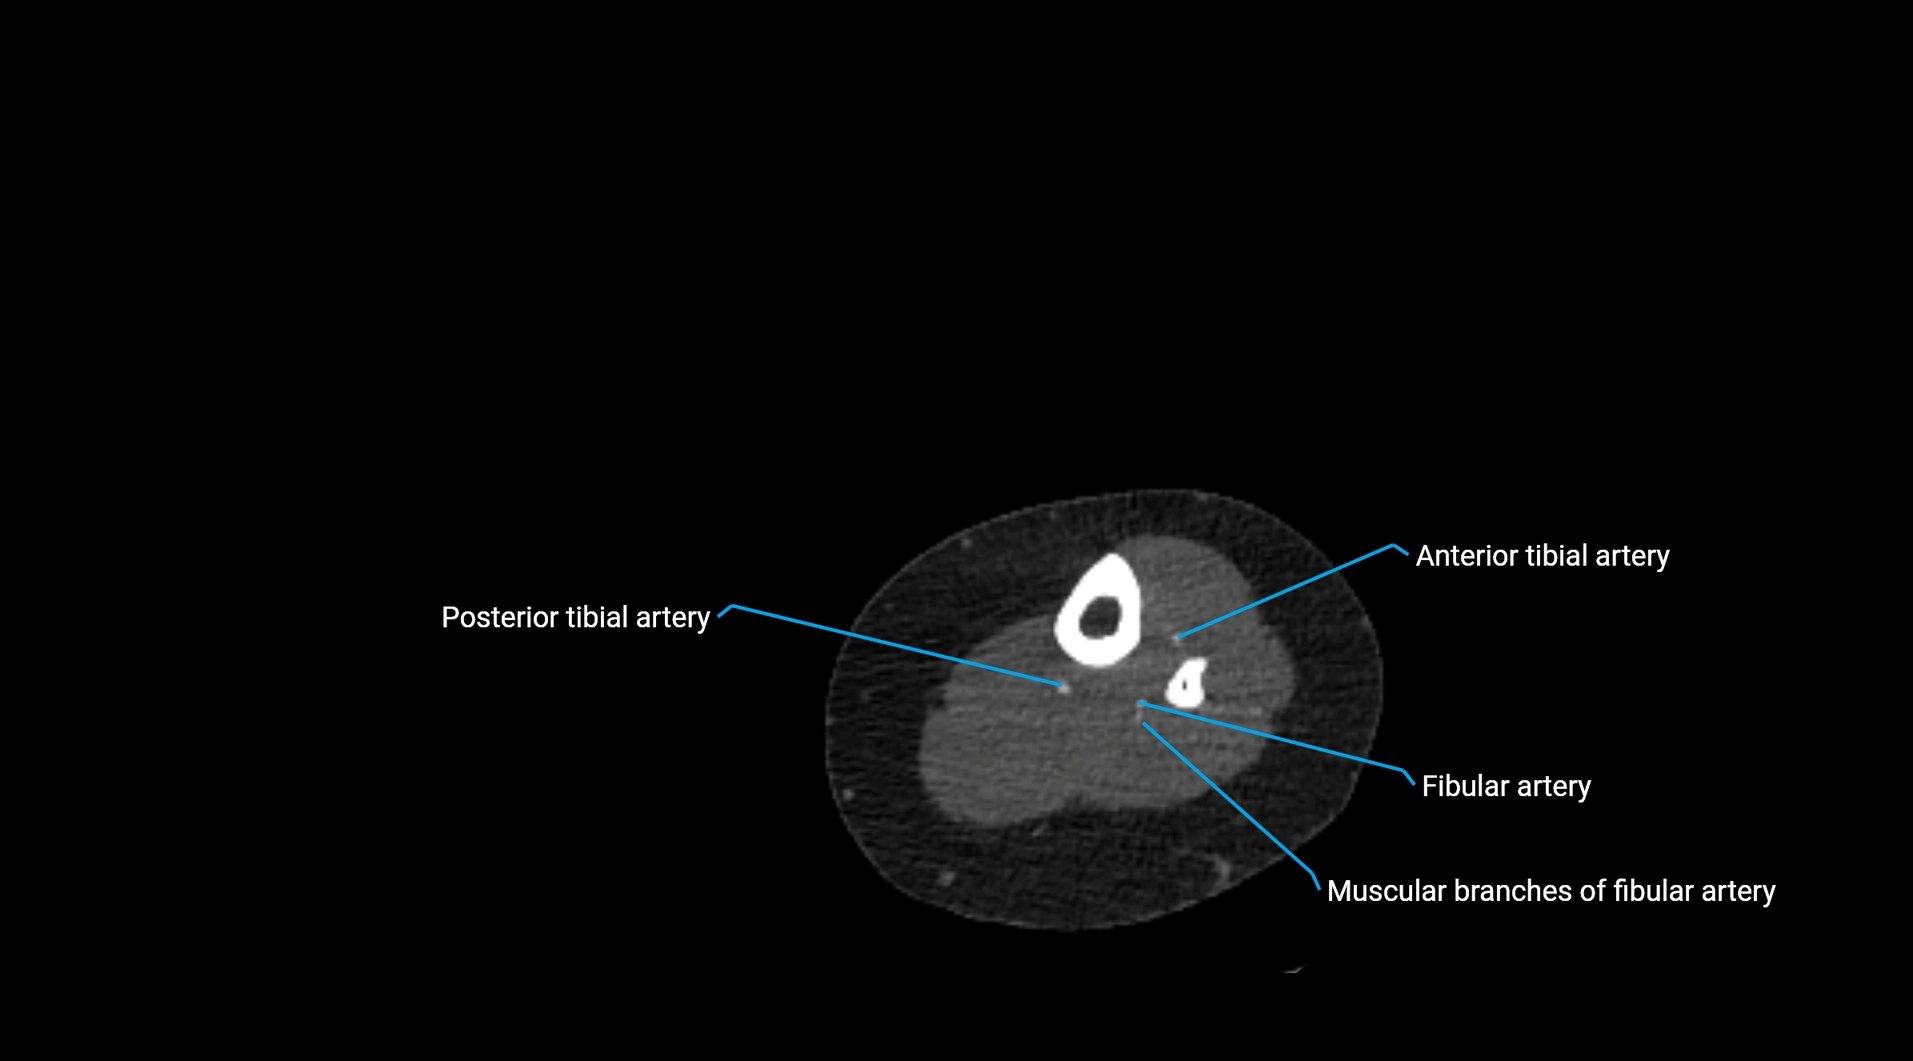

CT Appearance

Non-contrast CT:

• Appears as a tubular soft tissue structure anterior to vertebral bodies

• Calcified atherosclerotic plaques appear as hyperdense foci along the wall

• Useful for screening abdominal aortic aneurysm (AAA) size and mural calcification

Contrast-enhanced CT (CTA):

• Gold standard for abdominal aortic imaging

• Provides excellent detail of lumen, wall, aneurysm, thrombus, and branch vessels

• Multiplanar and 3D reconstructions help in aneurysm measurement, stent graft planning, and dissection evaluation

• Detects acute rupture, traumatic injury, or occlusion with high sensitivity

CT images

image